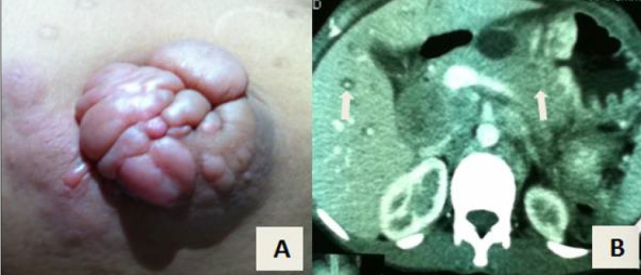

图片

一位有 Sister Mary Joseph’s nodule 的 73 岁女性,CT 示胰尾部 9.3x5.2 cm 占位,病理示转移性粘液性囊腺癌(图片来自文献 [7])